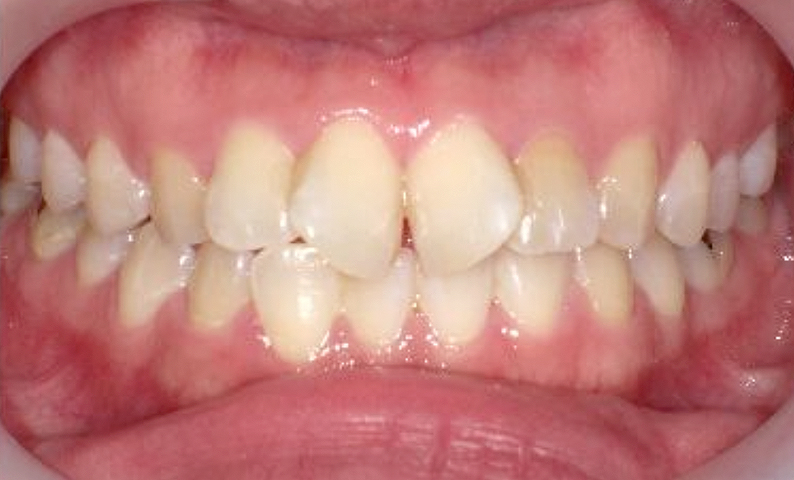

症例_025 上下顎の部分矯正

治療期間:13ヶ月金額:51万円+税女性前歯のガタガタ出っ歯

| Before | After |

|---|---|

|